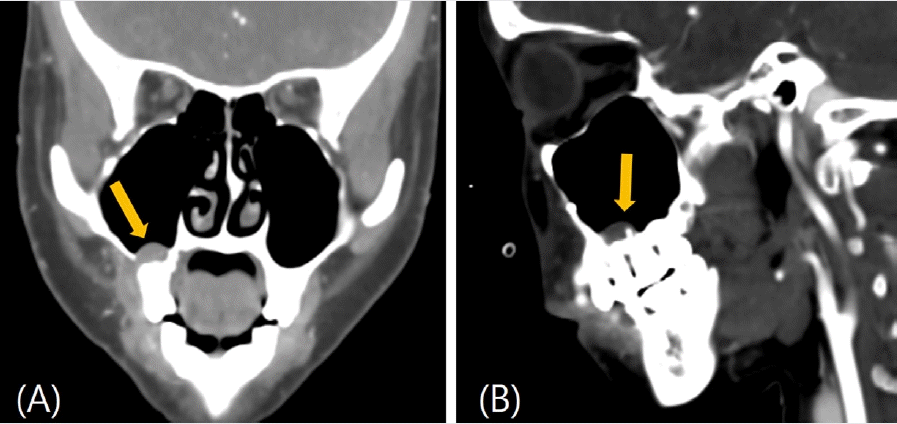

26세 여성이 수개월 전부터 발생한 원인미상의 지속적인 우측 상악 후방부의 잇몸 출혈을 주소로 의뢰되어 구강악안면외과 외래에 내원하였다. 빈혈 이외의 특이 병력은 없었으며, 콘빔 전산화단층촬영(Cone-beam Computed tomography, CBCT)과 파노라마영상을 포함한 단순 진단 영상에서 우측 상악 제2소구치와 제1대구치의 치근단 부위에 직경 12mm의 원형 낭종(Cystic lesion)으로 보이는 병소와 이에 동반된 협측 치조골의 골 침식(Bone erosion)이 관찰되었다(Fig. 1). 병소와 연관되어 있는 치아인 우측 상악 제2소구치와 제1대구치는 전기 치수검사(Electric pulp test)상 생활력이 있었으며, 필요시 술 후에 증상관찰 후 근관 치료를 시행하기로 계획하였다. 방사선 소견 상 반구형의 낭성 종괴, 부드럽고 매끈한 외부경계로 인해 상악동의 점액성 저류낭종(Maxillary mucous retention cyst)일 가능성도 존재했으나 콘빔 전산화단층촬영(CBCT) 상에서 치근부와 연결점이 보인다는 점에서 확률이 낮다고 판단했다[14]. 결국 치근단낭종으로 임시 진단을 내린 후 일주일 뒤 구강악안면외과 외래에서 낭종 적출술을 계획하였다. 빈혈의 기왕력이 있어 일반혈액검사를 실시한 결과, 헤모글로빈 6.7 g/dL, 혈소판 321,000/uL, 프로트롬빈 시간(Prothrombin Time, PT) 13.2 sec, 82.3%, INR 1.11, activated PTT(Partial Thromboplastin Time) 27.9로 외래 수술 시행 전 낮은 헤모글로빈 수치가 관찰되었지만 어지럼증과 같은 임상적 증상은 없었다.구강악안면외과 외래에서 1:100,000 에피네프린이 함유된 2% 리도카인(Lidocaine) 국소마취 하에 낭종 적출술을 시도했으나 수술 중 기구를 치근단 병소 부위로 접근하자마자 대량 출혈(Massive bleeding)이 발생하였으며, 국소적 지혈을 시도하였으나 전혀 지혈이 되지 않았다. 저혈량성 쇼크(Hypovolemic shock) 위험성이 있어 수술을 중단 후 응급실로 이송하였으며, 즉각적으로 적혈구 수혈 및 체액량 보존을 위해 0.9% 생리식염수로 정맥내 수액 공급을 진행하였다. 이어 구내에 발생한 출혈을 조절하기 위해 이어 영상의학과에 의뢰하여 접형구 개동맥(Sphenopalatine artery)과 상악후상치조동맥(Posterior superior alveolar artery)을 대상으로 색전술(Embolization)이 시행되었다(Fig. 2). 응급색전술은 겔폼(Gelfoam), 33% 아교(Glue), 코일(Coil)을 사용하였으며, 성공적으로 출혈을 조절할 수 있었다. 색전술을 시행한 다음날 적절한 혈관 폐색이 이루어졌는지 확인을 위해 전산화 단층 혈관 조영술(Computed tomographic angiography) 촬영을 진행하였다. 접형구개동맥이 폐색되어 있음을 확인하였고, 공급혈관(Feeding vessel) 내에 코일이 적절히 위치해 있었으며, 후상치조동맥에서 기원한 분지 내에서 병변 주변으로 이루어진 glue casting이 관찰되었다(Fig. 3). 이러한 영상 판독 결과를 통해 병변의 혈관 공급이 성공적으로 차단되었음을 확인하였다. 골내 혈관종의 다양한 방사선소견으로 인해 초기에 치근단낭종으로 오인되었음을 확인하였고, 이에 따라 낭종적출술이 아닌 골내혈관종의 수술적 절제를 계획하였다.색전술을 시행한지 이틀 째에 국소마취 하 혈관종의 절제술이 이루어졌다. 협측으로 접근하여 15번 외과용 칼(No.15 Surgical blade)와 골막기자(Periosteal elevator)로 조심스럽게 골막점막피판을 거상한 후에 종양을 주변 조직으로부터 박리하여 모스키토 지혈겸자(Mosquito forcep)로 종양을 제거하였다. 이 과정에서 치근단이 병변과 긴밀하게 연접하고 있는 상악 우측 제2소구치의 경우, 협측 골이 상당히 소실되어 있는 상태로 3도의 동요도를 보여 결국 발치를 하기로 결정하였다. 골 결손 부위와 발치와는 추후 임플란트 식립을 고려해 이종골 이식재와 흡수성 차폐막을 적용해 골이식을 시행하였다.수술적 제거 이후 2개월 추적관찰에서 재발 또는 잔여 증상은 관찰되지 않았다. 임상검사 및 방사선 영상검사에서 골 치유가 만족스럽게 이루어졌으며, 우측 상악 제1대구치에서 동요 또는 타진 통증 없이 환자는 무증상 상태를 유지하였다(Fig. 4). 수술 3개월 후 환자는 안정적인 골 치유와 충분한 각화 치은이 생성된 것을 확인되어 우측 상악 제2소구치부위의 고정체 식립을 위한 임플란트 1차 수술을 시행하였다. 이어 3개월 뒤 임플란트 치유지대주를 연결하는 임플란트 2차 수술 및 상부 보철물 수복을 완료하였으며, 경과 관찰 시 수술부위의 별다른 증상이나 재발의 증거는 없었고, 합병증은 발생하지 않았다.

Figure 1.

Panoramic X-ray (A) shows a lesion around the roots of the right maxillary second premolar and first molar. Cone Beam Computed Tomography (CBCT) sagittal (B) and coronal (C) views further depict the lesion in the right maxilla.